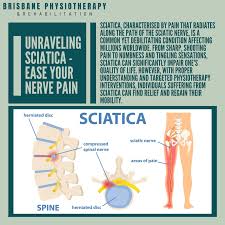

Download Sciatic nerve pain pictures